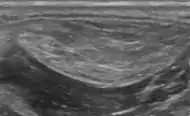

- Medical ultrasonography of a lipoma in the thenar eminence: It is hyperechoic compared to adjacent muscle, and relatively well-defined, with miniature hyperechoic lines.[21]